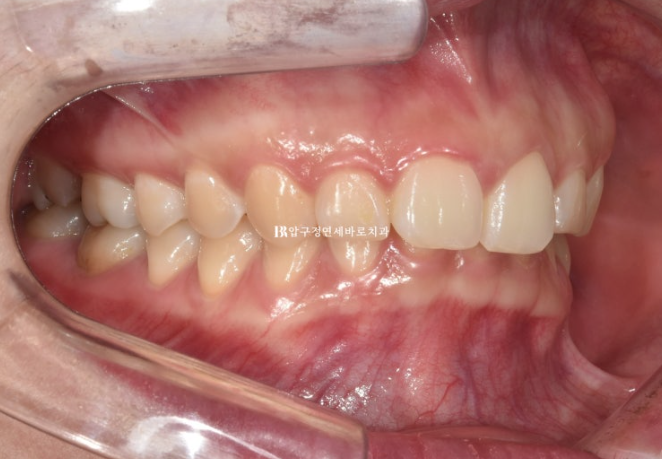

돌출입도 종류가 다양한데, 이렇게 앞니가 뻗쳐 있지 않으면서 잇몸쪽이 돌출이 되어 보이는 것을 잇몸돌출이라고 표현합니다.

위 작은어금니 두 개를 발치하고 인비절라인 교정 치료에 들어갑니다.

22.09

작은어금니를 발치한 지 일주일째가 된 날 인비절라인 첫번째 장치를 끼기 시작한 날 사진입니다.